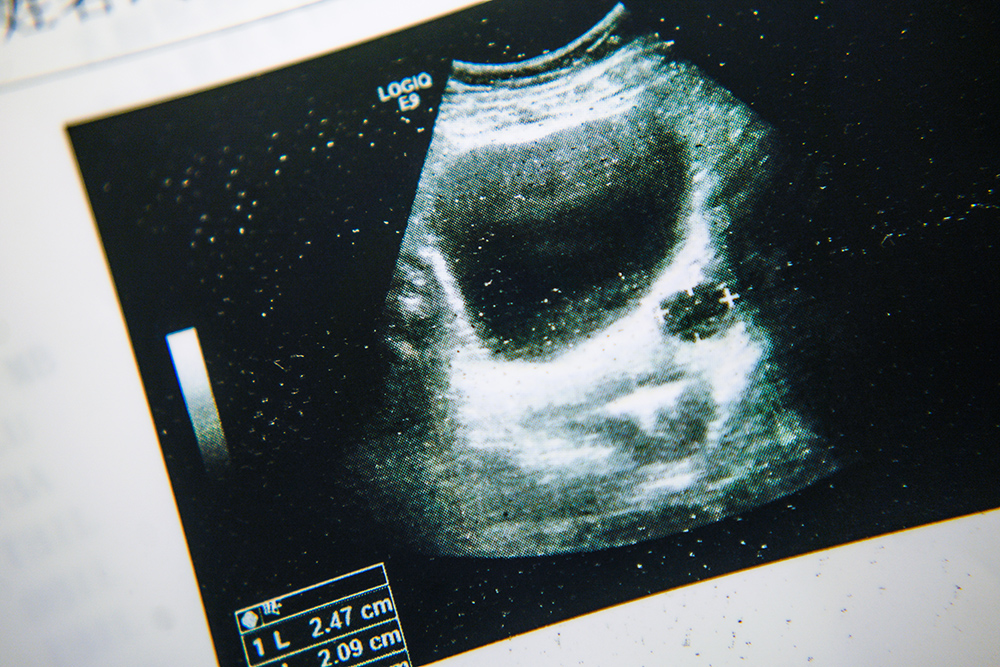

一切发生得非常快。一次搓澡的时候,我自己发现右乳有个硬物,后来被医生判定为恶性。隔天住院后,我做了全面检查,大概傍晚五点多,穿刺结果出来了,确认为恶性。那时候我身边一个人也没有,医生“宣判”的那一刻,我手脚冰凉,身体轻飘飘的。